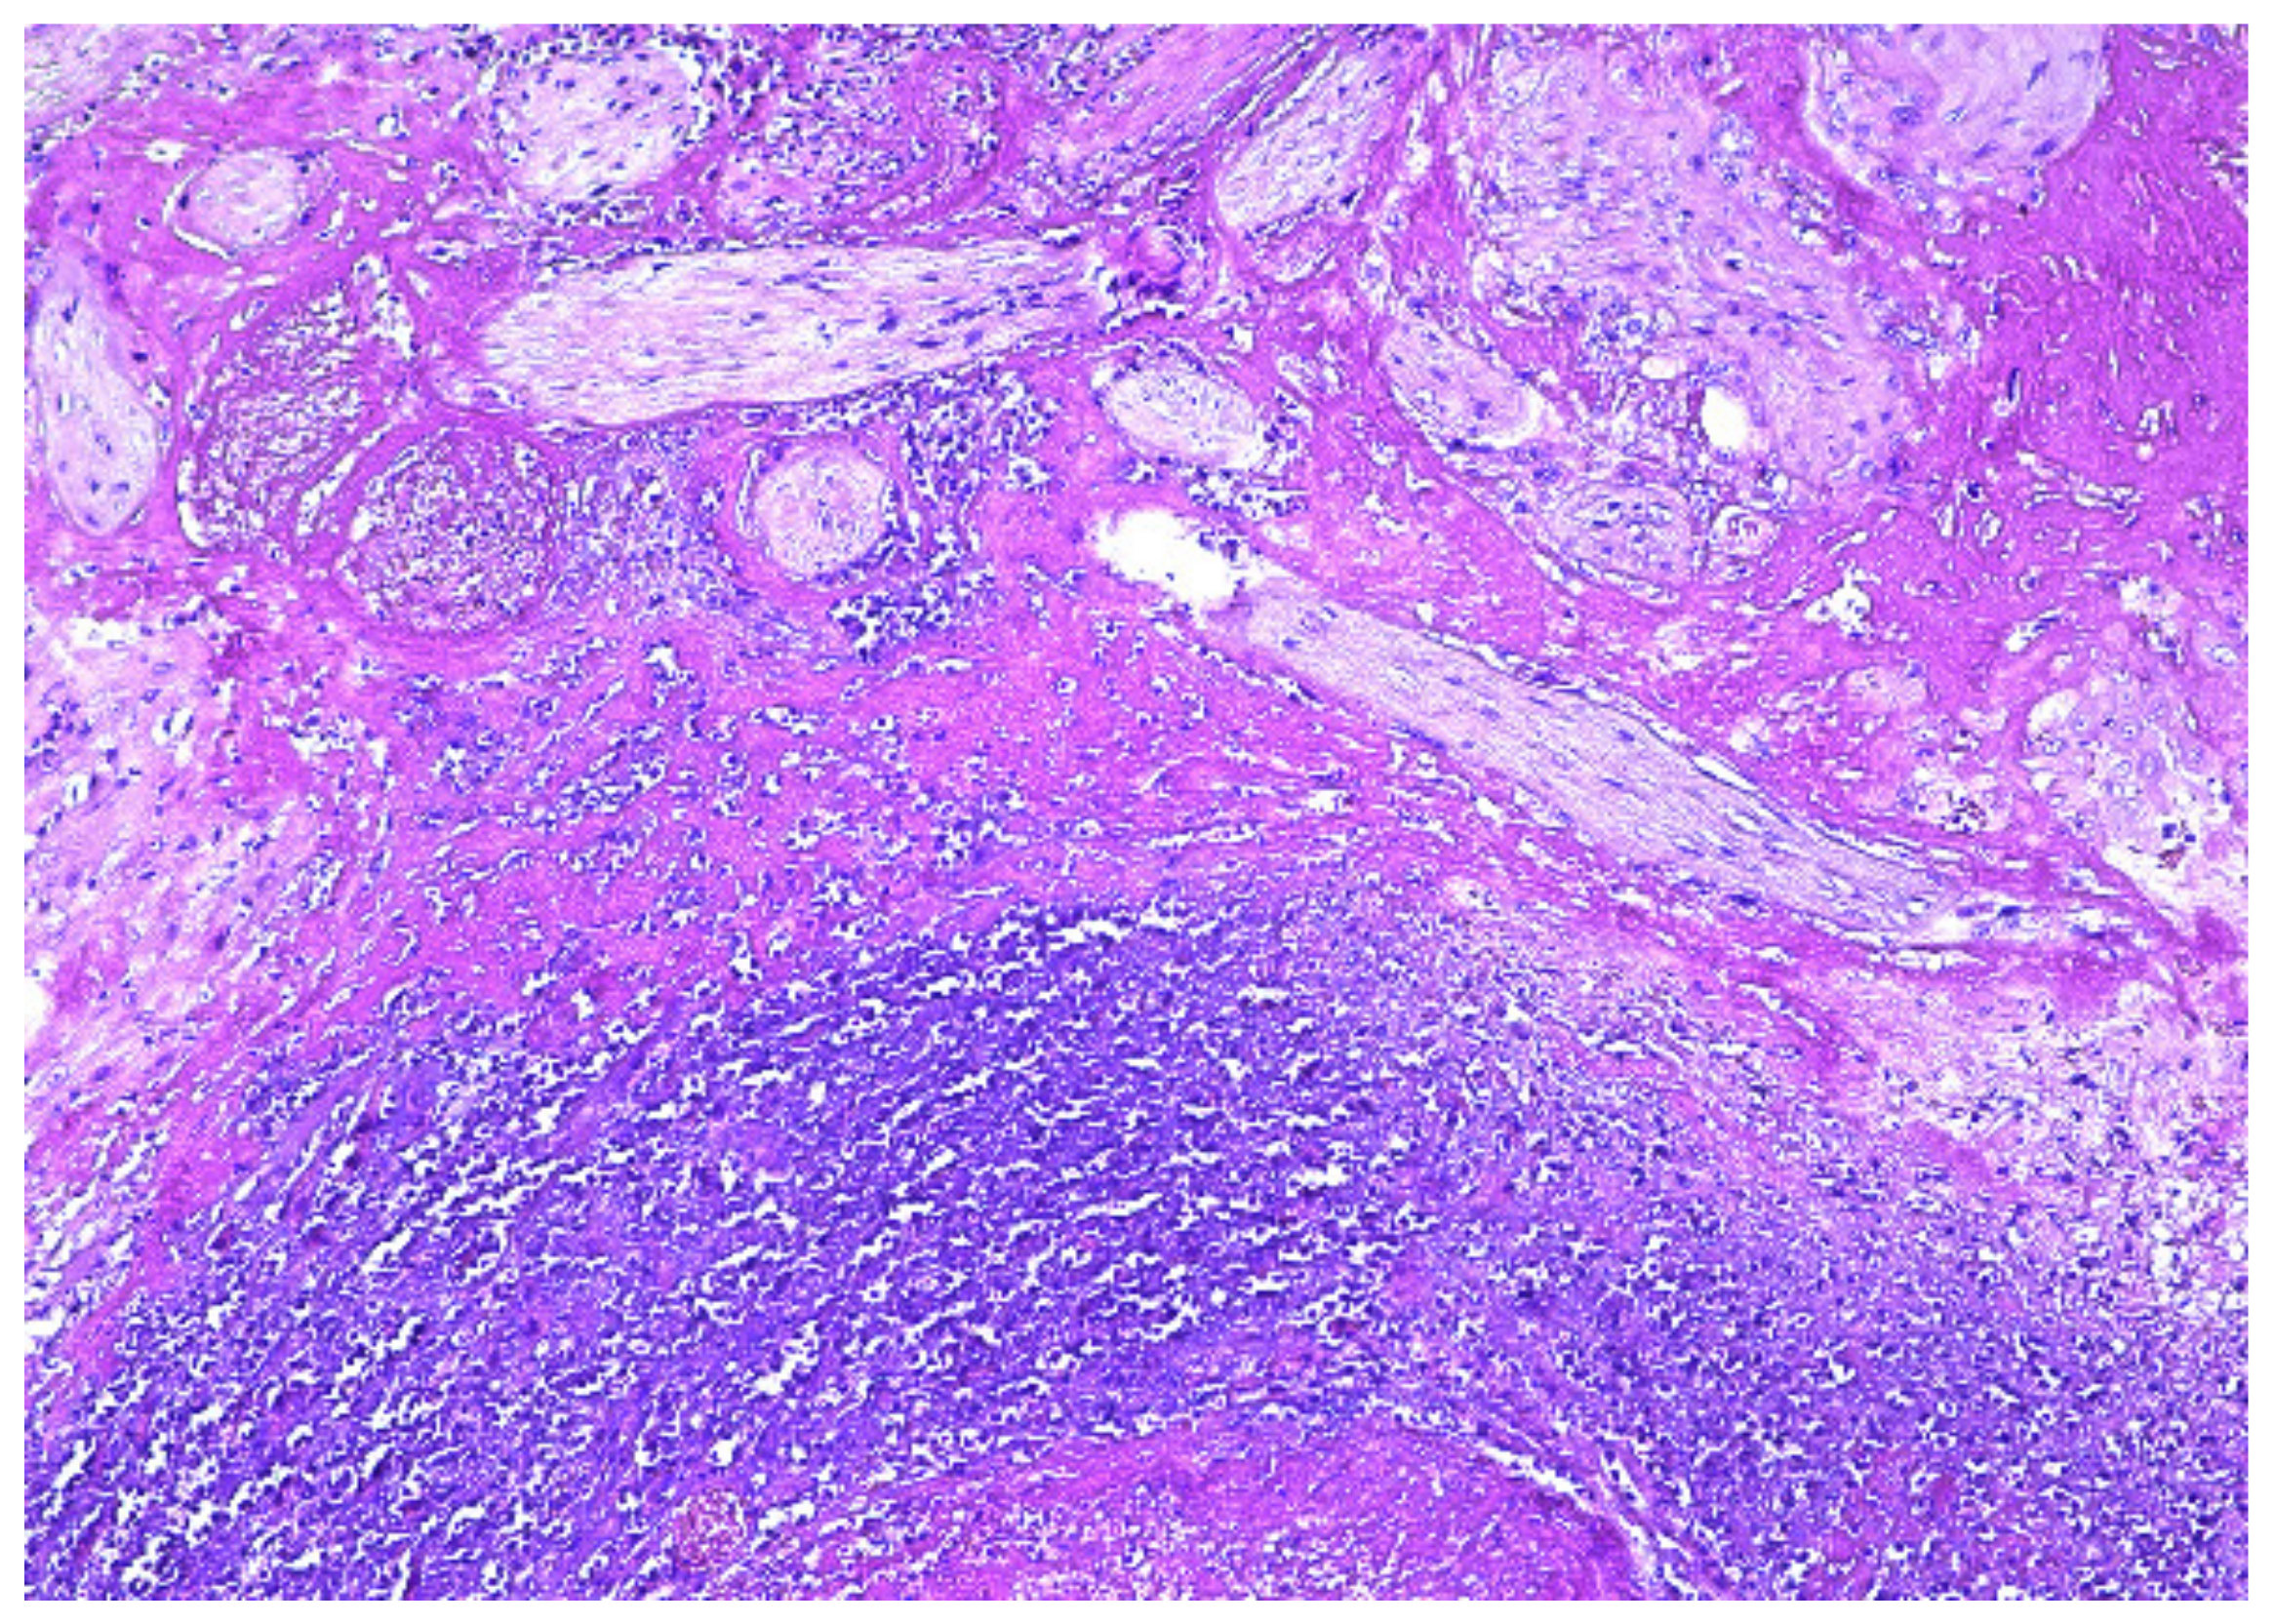

2. Case Presentation